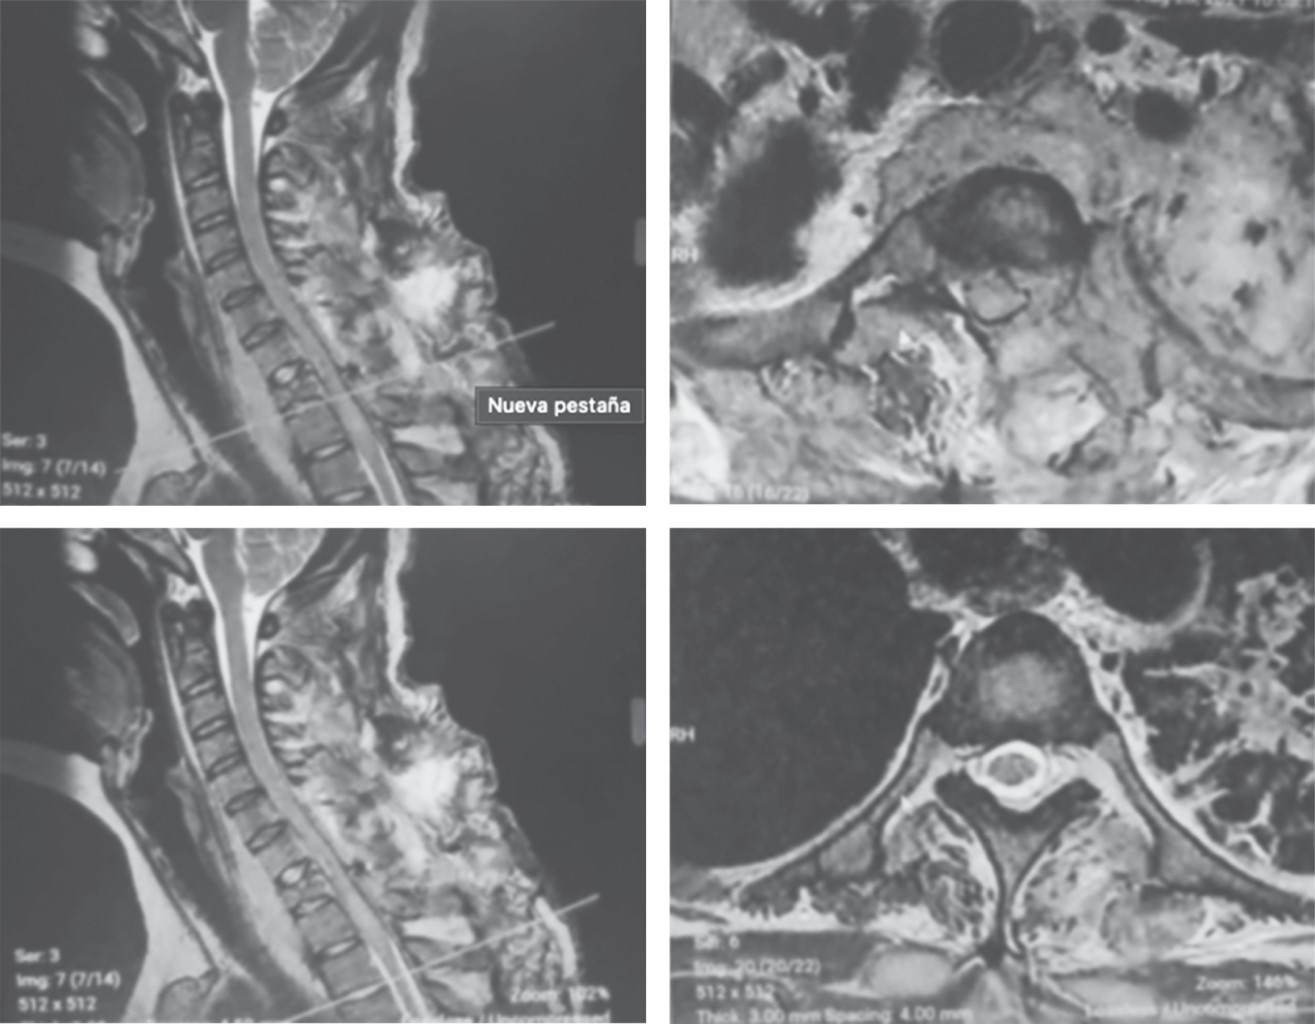

• 3. RMN de columna cervicotorácica: se observa osteólisis del cuerpo de T1, colección peridural de C6-T2, las cuales lateralizan el saco dural y médula hacia la derecha, además de generar compresión radicular bilateral y múltiples colecciones paravertebrales (Figura 2).

Figura 2